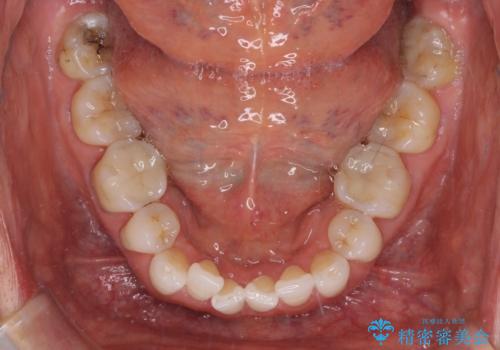

矯正治療の後戻り インビザライン・ライトでの再矯正

- 上下前歯を中心に、以前行った矯正治療の後戻りが気になるとのことで来院された患者様です。

後戻りは軽度であったため、インビザライン・ライトにて治療を行うこととしました。

矯正治療後は、再度後戻りすることを極力回避するために、下顎前歯の舌側を細いワイヤーを用いて保定することとしました。